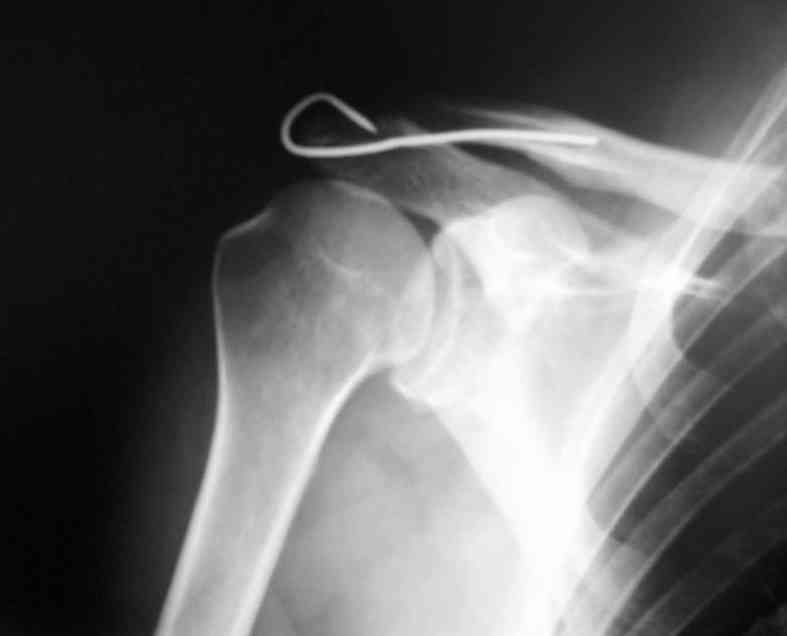

Здравствуйте.Извиняюсь за задержку. Фотографии фиксации АКС. Канал для ножки фиксатора формируется затупленным шилом, для уменьшения опасности перфорации кортикального слоя.

В некоторых клиниках активно применяли конструкции из никелида титана (с термомеханической памятью) с фиксацией за ключицу и клювовидный отросток. Сам не применял, но отзывы были хорошие а рентгенограммы красивые.